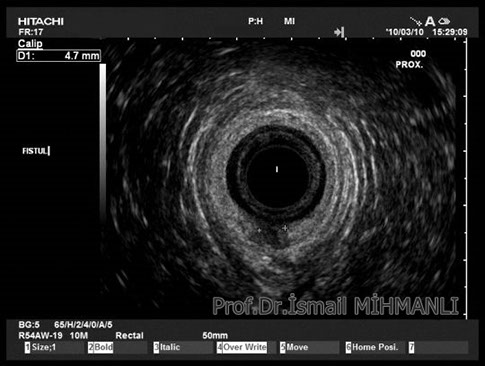

PERİANAL FİSTÜLLER Perianal fistül ve abselerin intersfinkterik anal bez iltihabından kaynaklandığı düşünülmektedir. Crohn hastalarında perianal enflamatuvar hastalık sıktır. İntersfinkterik mesafedeki enfeksiyon yukarıda rektuma, aşağıda cilde, yanlarda dış sfinkteri geçerek iskiyoanal mesafeye uzanabilir. Primer fistülün sfinkterler ile ilişkisini ve abse veya sekonder dal varlığını ameliyat öncesi bilmek, tedavi planı açısından önemlidir. İskiyoanal ve iskiyorektal mesafe tutulmamışsa hastalık daha kolay tedavi edilir. Bu mesafelerde abse veya sekonder bir dal varsa fistül komplekstir ve tedavisi kompleks olmayan fistüle göre değişik olabilir. Bundan dolayı, primer fistül traktı anatomik yerleşimine göre geleneksel olarak sınıflandırılır. Bu sınıflama dörde ayrılır: 1- İntersfinkterik (iç ve dış sfinkter arasında), 2- Transsfinkterik (dış sfinkteri geçerek iskiyoanal veya iskiyorektal mesafeye ulaşmış), 3- Suprasfinkterik (intersfinkterik plandan yukarı doğru uzanan traktüs puborektal kasın Genel Gaz ve Dışkı Kaçırma (Anal İnkontinans) Perianal Fistüller Rektal Tümörler Anal Tümörler Kabızlık Yazılarımız üstündeki bir seviyeden yana kıvrılarak tekrar aşağıya iskiyoanal mesafeye uzanmış), 4- Ekstrasfinkterik (sfinkterlerin dış tarafında rektumdan direkt olarak perianal cilde uzanan traktüs). Endoanal ultrason ile hem primer fistül, hem de varsa sekonder dal ve abse doğru bir şekilde tanınır. Endoanal ultrason ile fistülün anal kanala açılan kısmını (iç uç) görmek kolaydır. Bu hastalarda sfinkter defektlerine de rastlanmaktadır. Sfinkter defekti endoanal ultrason ile kolaylıkla tespit edilir. (bkz. anal inkontinans) Perianal fistül şikayeti olan hastaların az kısmında endoanal ultrason ile bir şey görülemez ise endoanal ultrason probuna ek olarak lineer prob ile anal kanal çevresine bakmak yararlıdır. Çünkü anal kanal bileşenlerinin uzağındaki bir enflamasyon ancak bu problar ile tanınabilir.

İntersfİnkterİk fİstül TRANSSFİNKTERİK FİSTÜL